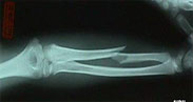

Las fracturas del cúbito y radio son las más frecuentes de la infancia y tienen lugar generalmente por caídas en lugares de recreo y durante la práctica deportiva. En la edad adulta los accidentes de tráfico y los deportes de contacto son las causas más frecuentes de lesión a este nivel. El tratamiento depende del tipo de fractura y grado de desplazamiento. Se realizará tratamiento conservador siempre que la fractura lo permita relegando el tratamiento quirúrgico a aquellas fracturas difícilmente estabilizables mediante escayola.